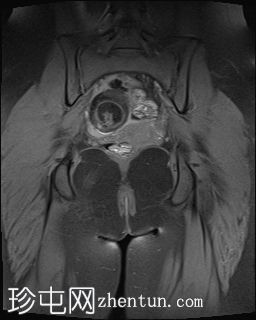

MRI扫描

冠状扫描

T1

右侧附件区可见较大囊性肿块,内含脂肪和液体,大小约为86毫米 x 60毫米。右侧血管蒂扭转,呈漩涡征。右侧卵巢可见增大充血的卵泡,为囊性肿块病变。左侧卵巢正常。